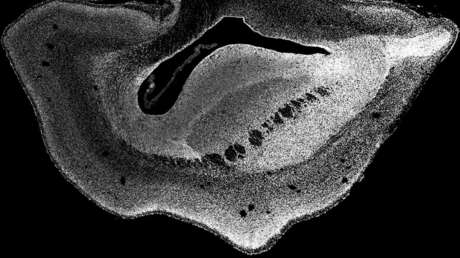

"De hecho, descubrimos que el neocórtex del cerebro del tití común se agrandó y la superficie del cerebro se plegó", dijo, citado por New York Post, Michael Heide, autor del estudio, publicado en la revista Science este julio y que plantea ciertas cuestiones éticas sobre la ingeniería genética. Los investigadores revelaron que los cerebros de los fetos pronto desarrollaron neocórtex más grandes y avanzados, un área que en los humanos constituye la mayor parte de la corteza cerebral.

Como resultado, concluyeron que el gen ARHGAP11B, específico de los humanos, pudo haber causado la expansión del neocórtex en el curso de la evolución humana. El neocórtex humano, una fracción del cerebro que juega un papel importante en los procesos del pensamiento, el lenguaje y la percepción, es la parte evolutivamente más joven de la corteza cerebral, y en nuestra especie es aproximadamente tres veces más grande que el de los chimpancés.